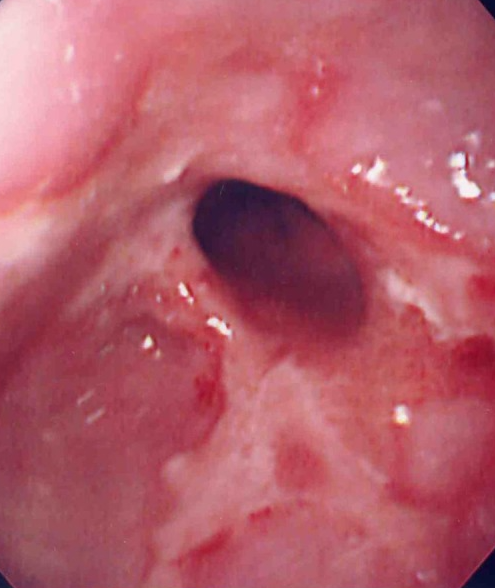

Gastroscopy. Green arrows: orifice of the gastrocolic fistula (Courtesy Dr. V. Penopoulos)